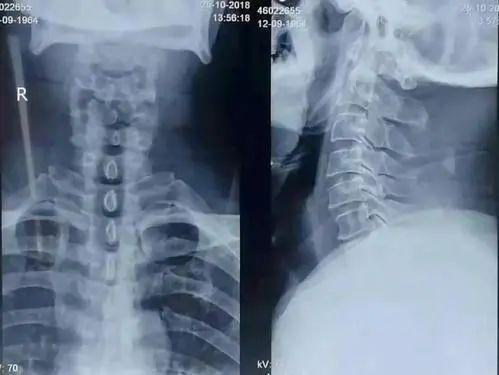

问诊、体格检查和辅助检查,缺一不可。临床经验丰富的按摩医生对病人实施任何手法治疗前,根据疾病的轻重缓急,一定需要有详细的颈椎病相关影像学检查资料(如颈椎的X线和核磁共振检查)。

颈椎的X线片

颈椎的核磁共振片